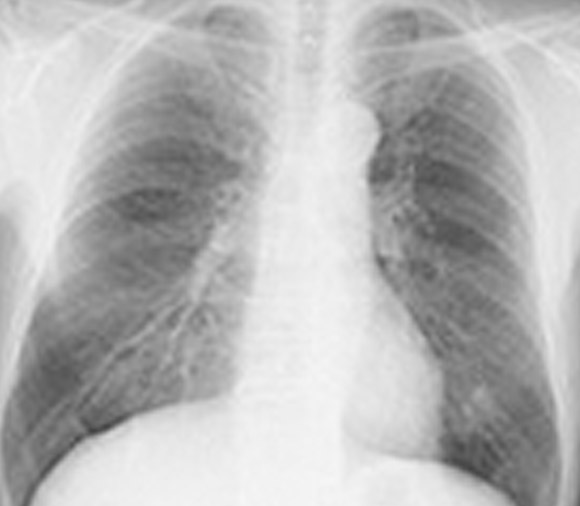

肺疾患や心臓疾患がないかを見るために撮影します。 手術前には、麻酔をかけて安全な手術を行なえるかを判断するために必ず行ないます。(術前検査) 透析患者さまには、胸部疾患がないかに加えて、心胸郭比(CRT)を計測するためにも撮影します。